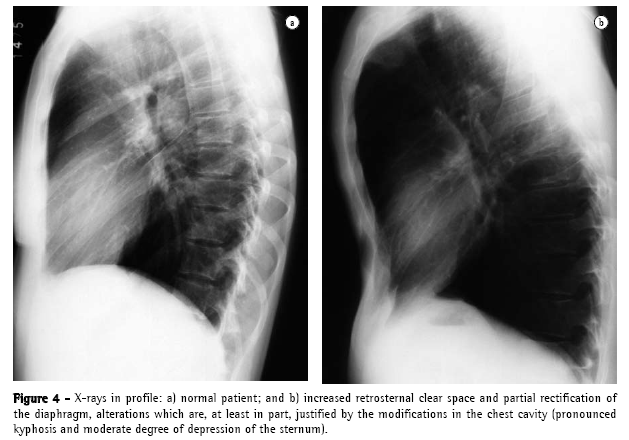

There are four principal causal mechanisms that can participate, together or in isolation, in the development of emphysema: hypoplasia (Figure 1), atrophy, hyperdistention, and partial or total destruction of the alveoli. Hypoplasia occurs due to failure in the development of the alveoli. Atrophy results from atrophy of alveolar walls, of former normal development. Hyperdistention represents distention of the alveoli beyond its normal capacity at maximum inspiration. Destruction is represented by loss of substance of alveolar walls, anatomopathologically distinct from atrophy.

In 1958,(13)a very important article waspublished, which pointed out errors in the preparation of pulmonary specimens in order to understand emphysematous lesions, describing better distention and fixation techniques. In a review of previous studies,(6) one author thus defined anatomopathological parameters, according to their distribution in relation to the lobes, (Figure 2): centrilobular, paraseptal or perilobular, panlobular and irregular.